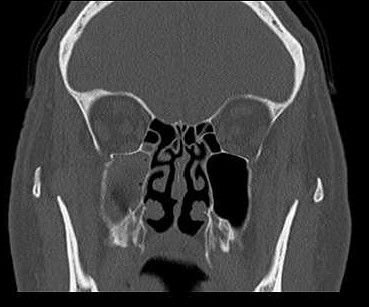

Distinguir radiográficamente un seno sano de uno enfermo no es tan problemático teniendo en cuenta su forma, que es inconsistente, con muchos lobulaciones, por lo tanto, en caso de sinusitis, se puede observar opacificación, engrosamiento de la mucosa y/o acumulación de líquido 17(Figura 3).

Diferentes estudios han demostrado que la SO podría representar entre el 45% y 75% de la opacificación unilateral del seno maxilar visibles en la TC 1,14,17.